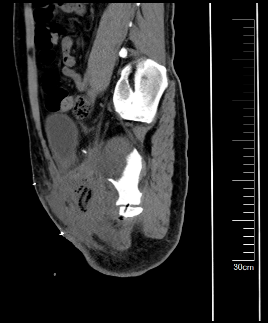

图片 2.png图片 3.png

术前CT